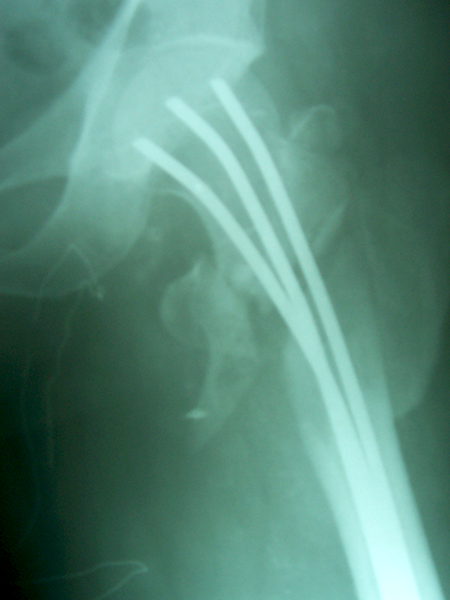

Case:9 Comminuted Intertrochanteric Fracture

Patient aged 75 years with Comminuted Intertrochanteric fracture treated with closed reduction & Ender’s nailing.

Pre-op Ap

Pre-op Lateral

Post-op Ap

Post-op Lateral

Post-op Distal End